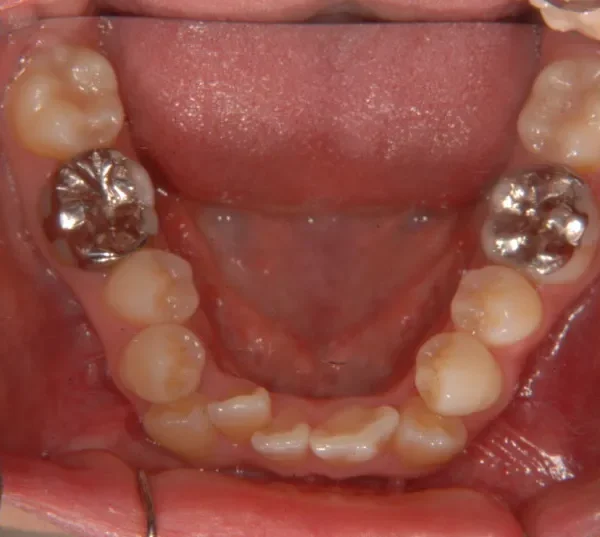

上下ガタガタで、下の歯は癒合歯(2本がくっついて1本の歯)です。

治療前と治療後で下の歯の銀歯がなくなっています。

これは銀歯の第1大臼歯を抜いて第2大臼歯、第3大臼歯の親知らずを使いました。